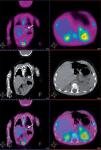

Estudio PETEl análisis cualitativo mostró un claro depósito focal de aumento de captación de 18F-fluoro-L-DOPA en la región de cuerpo de páncreas, anatómicamente bien definido por medio del estudio TC realizado conjuntamente. Dicho foco presentó un índice captación SUVmáx de 1,5 respecto a la captación de la cola y cabeza de páncreas. Además, se apreció una captación fisiológica de 18F-fluoro-L-DOPA en los ganglios de la base del cerebro, la vesícula biliar y la eliminación renal (fig. 1).

EvoluciónComo consecuencia de los hallazgos descritos anteriormente se procedió a la exéresis quirúrgica de la lesión apreciándose en el estudio histopatológico la existencia de un adenoma en la región de cuerpo coincidente con la localización descrita en el estudio PET-TC. Tras 5 meses de evolución, el niño se encuentra asintomático, sin necesidad de tratamiento farmacológico ni medidas dietéticas.